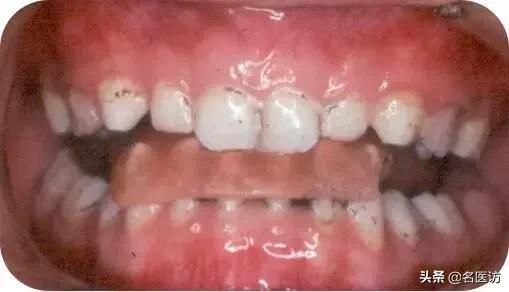

造成“地包天”的原因

地包天是什么原因造成的?

是我们当爸妈的造成的地包天哟?(⊙o⊙)

“地包天”的病因多得很,父母遗传只是其中一个,它还和先天性疾病、全身性疾病、儿童口腔不良习惯(前伸下颌、吮唇等)、不恰当的喂养方式(平卧喂养)、乳尖牙磨耗不足等各种因素有关。